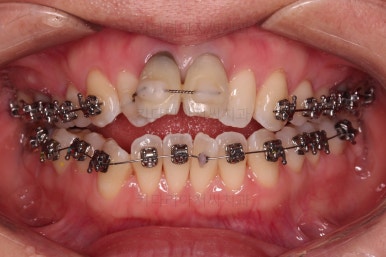

3. 치료과정

개방교합을 닫는 전략은 앞니를 약간 끌어내리고, 어금니를 앞니 위치로 약간 올려서 균형을 맞추는 건데요.

장치 부착은 윗니 어금니부터 했습니다.

미니스크류를 다양하게 활용하여 어금니 높이를 조절합니다.

여전히 앞니는 내버려둔 채로, 윗니는 어금니쪽만 진행하며 아랫니도 장치를 부착했습니다.

난이도가 매우 높은 치료인만큼 미니스크류의 구성과 장치 구성도 매우 복잡했는데요.

윗니 어금니를 뒤로 밀면서 앵글씨 2급 부정교합을 개선해 주고, 높낮이를 조절하면서 개방교합을 개선해 줍니다.

개방교합도 많이 다물어졌고, 2급 부정교합도 매우 많이 개선되었네요.